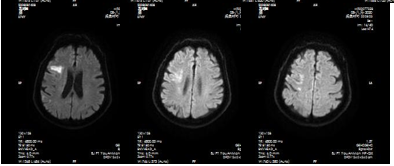

影像诊断

病历夹什么径技·第151期|串联营病历夹:京广连营_https://www.jmylbn.com_新闻资讯_第72张

病历夹什么径技·第151期|串联营病历夹:京广连营_https://www.jmylbn.com_新闻资讯_第73张

病历夹什么径技·第151期|串联营病历夹:京广连营_https://www.jmylbn.com_新闻资讯_第74张

<<滑动查看下一张图片>>

结论:颅脑CT提示左侧基底节、放射冠区腔隙样软化灶。颅脑DWI提示双侧小脑、桥脑、中脑、双侧海马、双侧枕叶、右侧丘脑及右侧胼胝体多发急性脑梗塞。颅脑MRA提示基底动脉及双侧大脑后动脉未见显示;右侧大脑中动脉中-重度狭窄;脑动脉硬化。初步诊断为急性后循环脑梗死,基底动脉闭塞。